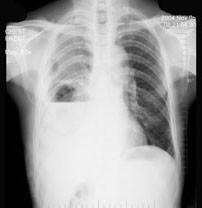

问题 男性患者,64岁,咳嗽高热多日,无痰中带血,X线检查如图所示,最合理的诊断是 ( )

选项 A、右肺不张 B、右支气管扩张 C、右侧胸腔积液并肺脓肿 D、右肺炎 E、右侧胸腔积液

答案 C